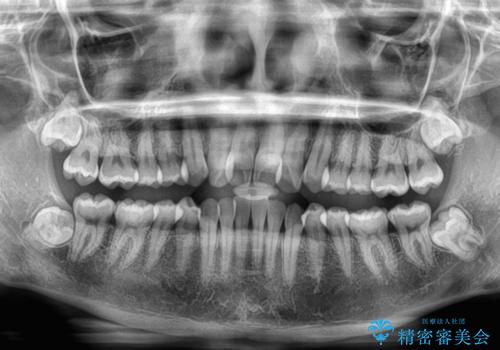

- 上顎前歯のクロスバイトを気にして来院された患者様です。

ワイヤー矯正でもマウスピース矯正でも対応可能でしたが、マウスピースによる自己管理に一切の自信がないとのことで、ワイヤー装置にて矯正治療を行うこととしました。